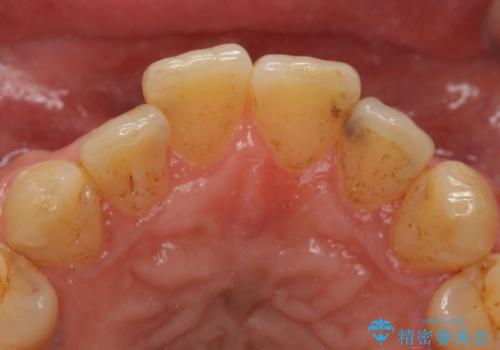

- 左の前歯が黒いとのことで来院。

1番目の歯は小さい虫歯があったのでプラスチックの樹脂で治療をしました(保険内)。

2番目の歯は二箇所虫歯があり、プラスチックの樹脂で治療するとつぎはぎみたいになってしまうので、

白い被せ物(ジルコニアクラウン)で治療しました。